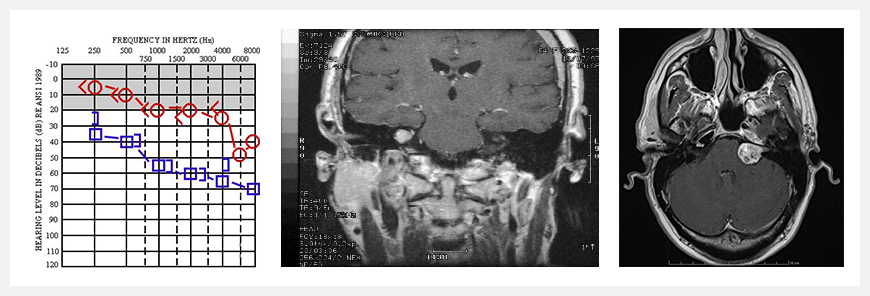

1、MRI檢查:當(dāng)今大多數(shù)的聽神經(jīng)瘤通常是在頭疼,急性聽力障礙或者頭部核磁共振成像(頭疼)時(shí)被偶然的診斷出來的。對于有神經(jīng)纖維瘤家族史的成員經(jīng)常檢查很重要,如果核磁共振成像檢查操作正確的話,MRI能夠發(fā)現(xiàn)直徑1 mm以上腫瘤,腫瘤T1WI呈低及稍低信號,T2WI呈高及 稍高信號,囊性則呈長T1長,12信號。

2、其他診斷方法:聽力功能測試(聽力)、聲學(xué)誘發(fā)電位(醫(yī)學(xué)意義的客觀測量方法)、對于平衡器官卡路里刺激的檢測